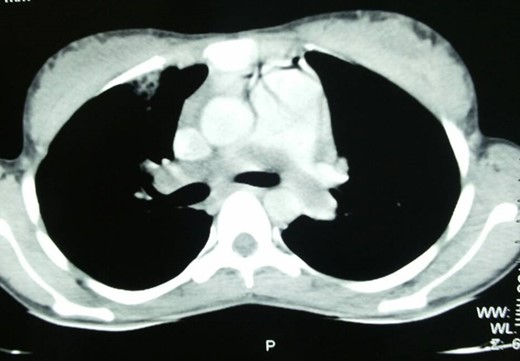

A 25-year-old lady was admitted in the pulmonology ward with the diagnosis of pneumonia. The patient had presented with a history of progressive shortness of breath, chest pain and persistent cough with occasional haemoptysis. She had a history of being treated with antibiotics and anti-TB drugs in outpatient basis. She had had spontaneous abortion 8 months back. Since her symptoms were persistent and her general condition was deteriorating, she was admitted to the ward. On examination, she had crepitations in bilateral chest and an oxygen saturation of only 80%. Chest X-ray showed bilateral infiltrations. CECT chest was done, which revealed pulmonary embolus occluding the main pulmonary artery, and right and left pulmonary arteries (Fig. 1). Venous Doppler did not reveal thrombosis of the lower limbs or IVC. Pulmonary thromboembolectomy was done and embolus (Fig. 2) was sent for histopathological examination. The examination revealed it to be metastatic choriocarcinoma (Fig. 3). Serum beta-human chorionic gonadotrophin (HCG) level was found to be significantly high. CECT pelvis and head were negative for pelvic and CNS metastases. She was managed further with chemotherapy (EMACO regimen) with excellent response to the treatment.